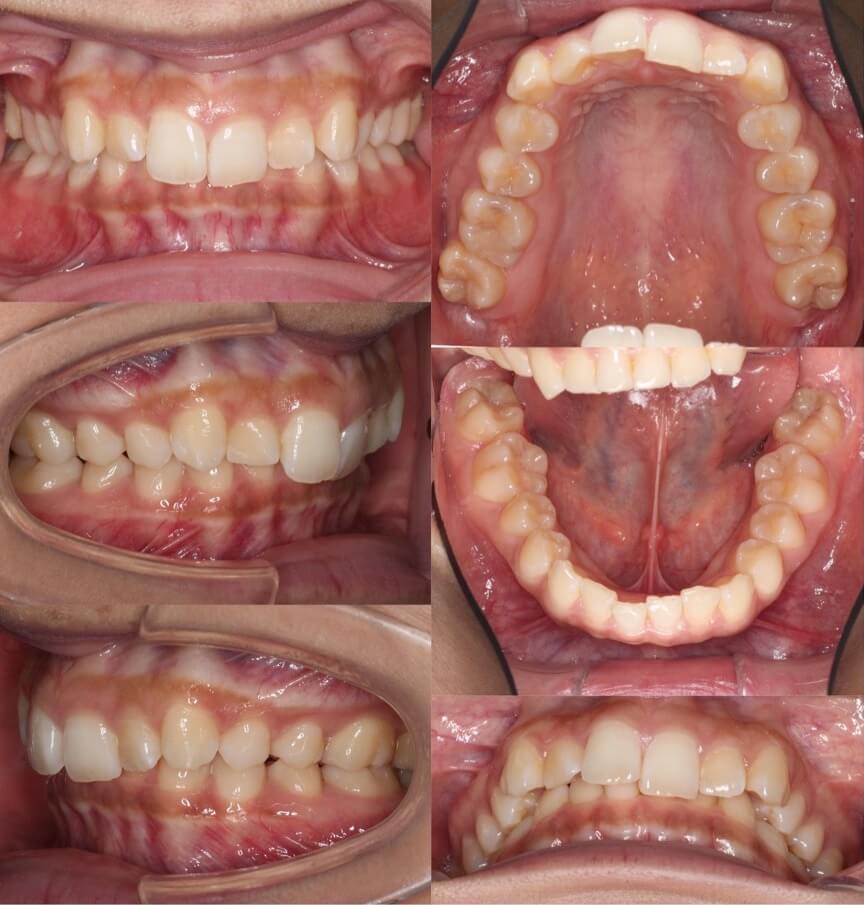

高校生女子・マウスピース型矯正

<顔のビフォーアフター>

<症例概要>

主訴:上の前歯の歯並び

年齢・性別:15歳女子(高校生)

住まい:千葉県佐倉市

症状:過蓋咬合・叢生

治療方針:上下顎前歯前方傾斜・ストリッピング

治療装置:マウスピース型矯正装置(アライナー装置)

治療期間:11か月

アライナー枚数:17+11ステージ

リテーナー:上プレートタイプ・下フィックスタイプ

治療費用:990,000(税込)

代表的副作用:痛み・治療後の後戻り・歯根吸収・歯髄壊死・歯肉退縮

▶︎その他の副作用

※マウスピース型カスタムメイド矯正歯科装置は完成物薬機法対象外の矯正装置であり、医薬品副作用被害救済制度の対象とはならない可能性があります。

過蓋咬合のケースです。マウスピース型矯正装置を使用し、非抜歯にて治療を行いました。途中から顎間ゴムも使用して、噛み合わせの仕上がりも問題ありません。マウスピース矯正はケースによっては従来型の矯正治療より早く終える事ができる事もあります。「早く」「痛くなく」なら「目立たない」という理由以外にマウスピース装置を選択するメリットはありますよね。